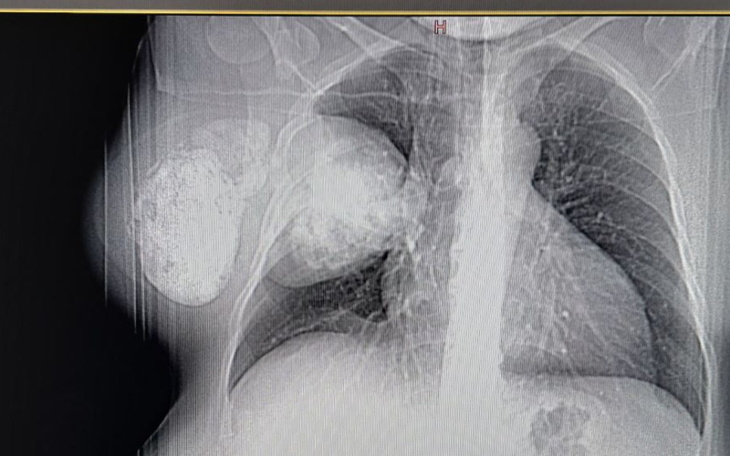

Здравствуйте, мои дорогие! Меня зовут Ольга, до недавнего времени я никогда не думала, что мне придется обратиться за помощью, теперь мне нужна поддержка! Моя жизнь разделилась на «до» и «после», когда мне поставили диагноз опухоль в груди. Я одна воспитываю 9-летнего сына и очень хочу, чтобы у него была живая мама! Мне нужна срочная операция, после которой мне предстоит длительная реабилитация, к сожалению, в этот период я не смогу работать! Мне действительно нужна твоя помощь! Очень надеюсь на вашу поддержку и всем спасибо! Большое спасибо!!!